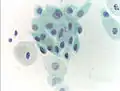

Normal squamous epithelial cells in premenopausal women

Atrophic squamous cells in postmenopausal women